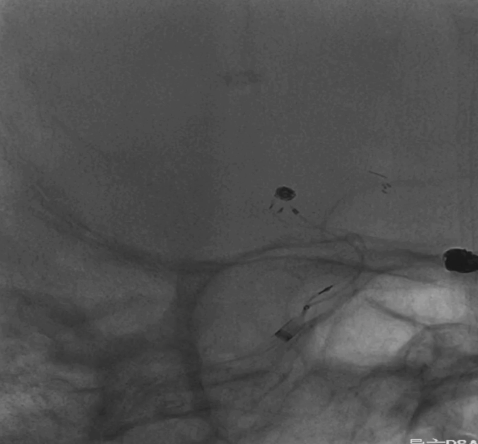

6F Envoy DA在泥鳅导丝辅助下超选至右侧颈内动脉海绵窦段后膝。

Asahi 0.014微导丝塑形后辅助Echelon 10微导管进入A2远端备支架释放。

Asahi 0.014微导丝导引璞慧 0.017微导管进入动脉瘤内。